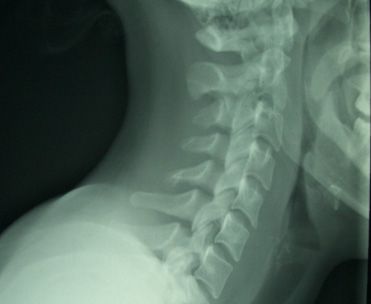

A woman in her 20s presented after 9 days of sore throat and subjective fevers followed by neck stiffness. The pain was exacerbated by swallowing and any neck motion. A radiograph of the young woman with meningeal signs shows widening of the prevertebral soft tissues. At first glance the soft tissues may appear normal, but there should be a step-off around C3-4, which is not noted in this film. Normal prevertebral soft tissues should measure less than 6 mm at C2 and less than 22 mm at C6.